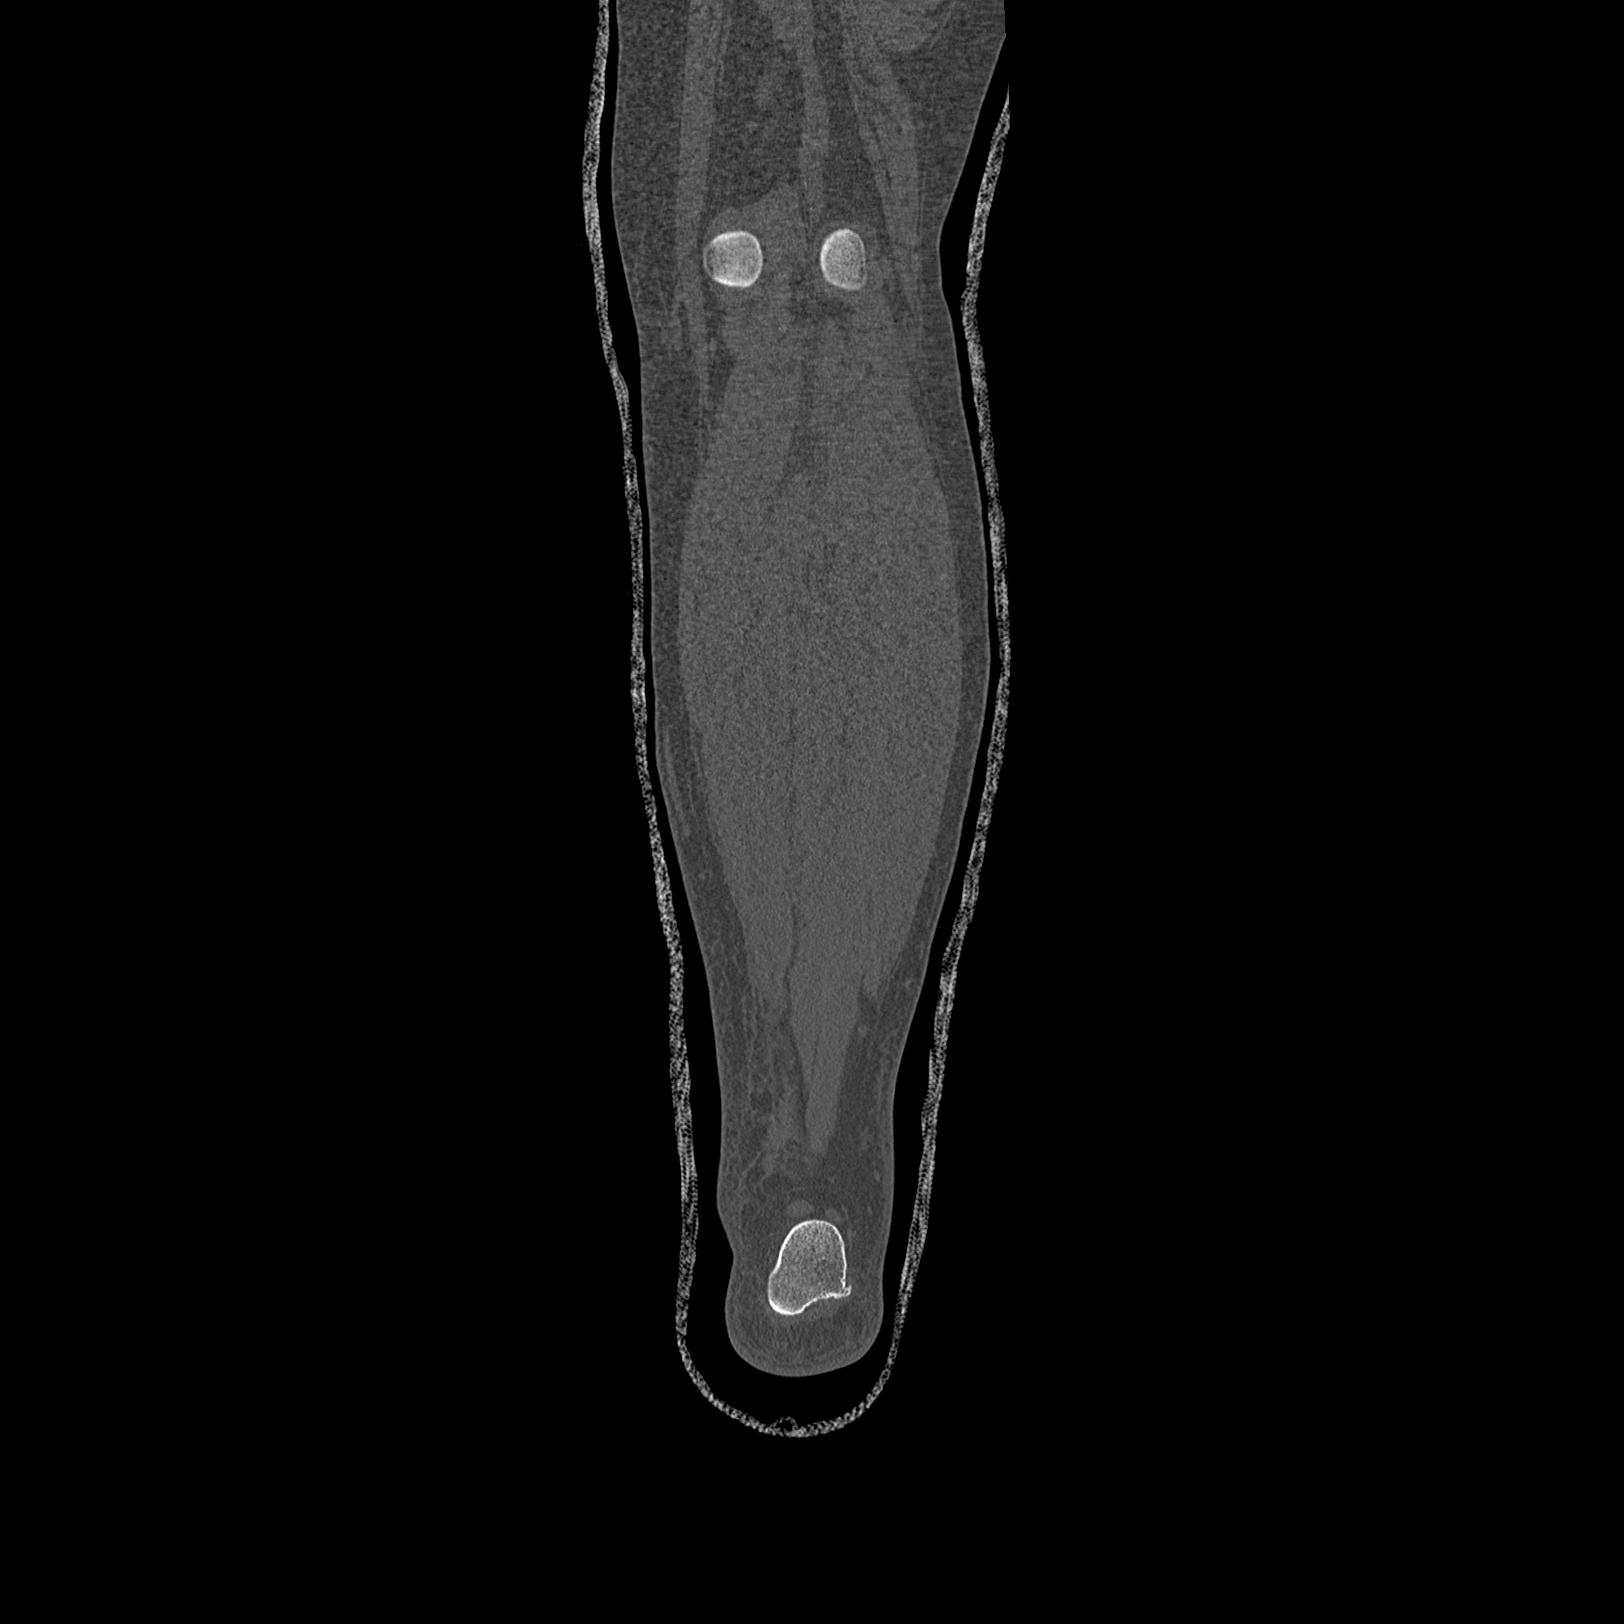

56476 8/28 4R 1/21 2R 左足関節 デジカメ写真 72歳女性 右足関節AS